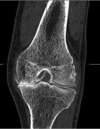

• Autres examens radiologiques : scanner articulaire (Arthro-TDM), IRM, Scintigraphie osseuse, TEP-Scan etc...

Scanner articulaire (Arthro-TDM) : pincement articulaire asymétrique entre fémur (en haut) et tibia (en bas), et contact os sur os témoignant de la disparition du cartilage au niveau du compartiment interne, mais pas externe ou le cartilage et le ménisque sont préservés)